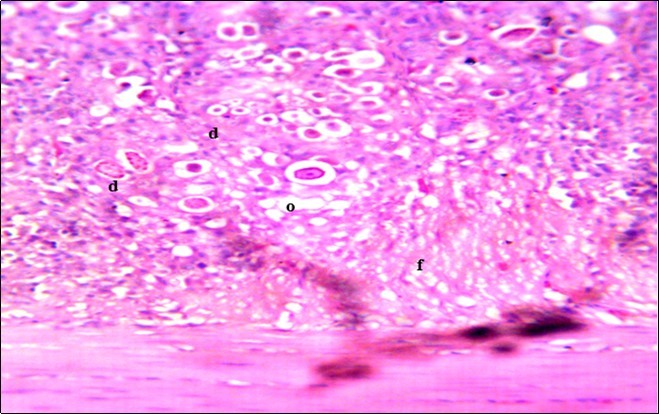

Figure 4.Photomicrograph of caecum of chick administered 20000 Oocysts of Eimeria tenella and untreated showing generalized degeneration of the caecal glands (d) with massive Ocysts (o) and gametocytes (g) largely within the caecal glands X250 (H&E).

In this study, the reduction in oocyst count observed in the treated group was compared with amprolium could be attributed to the presence of a bioactive compounds azadiractin A which is known to bind membrane cholesterol, altering the integrity of the parasite membrane, resulting in loss of homeostasis and eventual death of the parasite 29]. Also, limonoids contained in NeemAzal® inhibit protein digestion and uptake of vitamins and minerals by the parasites in the gut 17. This action results in impaired nutrient utilization, reduced growth, and multiplication of the parasite which could contribute to the reduced oocyst count observed. Extracts of neem and mahogany when used individually have been reported to reduce oocyst count in avian coccidiosis 11,12. The observed reduction in oocyst count and the significant increase in weight gain of the birds when treated with NeemAzal®, as compared with the negative control group could probably be due to the inhibition of inflammation in the intestinal mucosa which is suggestive of an increased nutrient absorption across the intestinal wall and enhanced feed conversion ratio compared to the negative control this is in agreement with reports by Nwosu et al.12 and Biu et al.11 who also reported an increased weight gain and feed conversion ratio in birds treated with only Khaya senegalensis extracts and Azardiractaindica, respectively. The observed increase in RBC and haemoglobin concentration is indicative of the erythropoieticability of the NeemAzal®, which is beneficial since the Eimeria parasite in the epithelia of the intestines causes bloody diarrhoea and consequently anaemia (Table 1). This finding is in consonance with 15 who reported an anti-anaemic effect of Khaya Senegalensis on phenyl hydrazine-induced anaemia in rats. Neem has been shown to possess anti-anaemic properties in rats 14. The significant increase in mean weight gain in treated birds when compared to the negative control is possibly due to the inhibition of inflammation in the intestinal mucosa which is suggestive of an increased nutrient absorption across the intestinal wall and enhanced feed conversion ratio compared to the negative control. Nwosu et al.12 and Biu et al.11 reported an increased weight gain and feed conversion ratio in birds treated with only Khaya Senegalensis andAzadiractaindica extracts, respectively. In a similar study, Neem acts like toltrazuril exhibiting anticoccidial. In addition, exposure of broiler chickens to 20000 Oocysts of Eimeria tenellacaused generalized degeneration of the caecal glands with massive Oocysts and gametocyts within the caecal glands with fibrosis (Figure 3, Figure 4 & Figure 5), however, broiler chickens treated with NeemAzal® post exposure to 20000 Oocysts of Eimeria tenella, shows equal numbers of caecal tissues with non-observable histopathological lesions (Figure 4), possibly due to the antioxidant and anti-coccidian effects of NeemAzal®. The exact mechanism of action of neem against coccidian parasites is unknown, but a report by the National Research Council 1992 30, suggested that aqueous neem leaf extract, when taken orally, produces an increase in red cells, white blood cells and lymphocyte counts thus enhancing the cellular immune response, increasing antibody production and so most pathogens can be removed before they cause the symptoms associated with disease this was in agreement with this study as seen in Table a remarkable increase of the RBCs.

In addition, the generalized degeneration of the caecal glands, moderate numbers of gametocytes within the glandular regions with fibrosis which underscores reparative process in response to injury evoked by coccidiosis in the chicks which was perhaps brought about by the antioxidant and chemotherapeutic effect of NeemAzal®. The observed increase in RBC and hemoglobin concentration (Table 1) is indicative of the erythropoieticability of NeemAzal®, which is beneficial since the Eimeria parasite in the epithelia of the intestines causes bloody diarrhea and consequently anaemia. This finding is in consonance with 15 who reported an anti-anaemic effect of Khaya senegalensis on phenyl hydrazine-induced anaemia in rats. If the results of this study are juxtaposed with the results of the previous studies on potent antioxidant, hepatoprotective and mitigative role of methanolic extracts of Azadirachtaindica,in both natural and experimental infection with Eimeria species and can be deduced that, NeemAzal® could be said to be a potent antioxidant, chemotherapeutic and tissue protective agent. This study also answered a question on further study advocated to determine the maximum safe levels of neem supplementation because the higher doses, due to its bitterness, may show adverse effects on feed intake which will change the performance parameters of birds (Figure 6 and Figure 7) . Light microscopic inspection of hematoxylin and eosin-stained sections revealed that the epithelial cells of the Cecum were infected by E. tenella(Figure 3 and Figure 4). The results of the safety study showed that exposure of chickens to NeemAzal® at 200mg/kg body weight did not alter the histoarchitecture of liver and kidney (Figure 6 & Figure 7) which is similar to the work conducted in the same environment by a group of Scientists 34. It is therefore recommended that NeemAzal® could be used as a coccidiostat to replace the expensive anti-coccidiostats in the market.